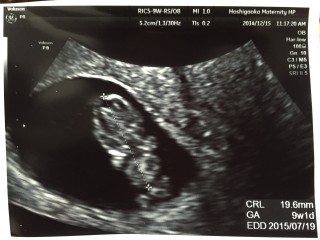

初めての妊娠です。エコーで赤ちゃんが動いてるのを見た時、すごく嬉しかったです。次の検診まで何日かありますが、成長している姿が見れる事を期待しています。

今回初めて手足がはっきり見えました!くねくねと動いているのがあまりにも可愛くて笑ってしまいました(^O^)次回も楽しみです♪

手足をピクピク動かしてました☆